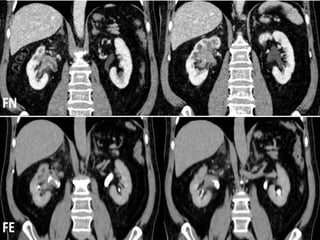

• #42 TUMOR UROTELIAL PIELOCALICIAL. Reconstrucciones coronales de TCMD en fase nefrográfica y en fase excretora que demuestran la existencia de una lesión neoproliferativa piélica derecha. La lesión presenta densidad de partes blandas y realza con contraste en FN, mostrándose como un defecto y distorsión de la repleción en FE.

• #43 CARCINOMA DE CÉLULAS TRANSICIONALES PIÉLICO. Imágenes axial y coronal en FN que muestran formación sólida hipercaptante ocupando pelvis renal izquierda. En las imágenes axial y coronal en FE la lesión se identifica como un defecto de repleción.